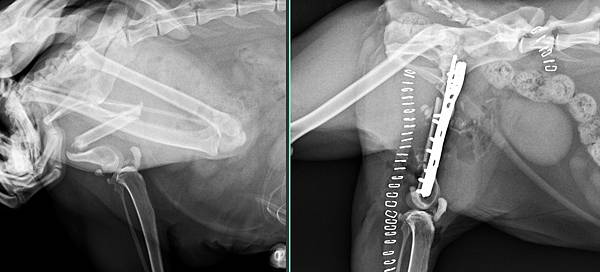

菜包是一位骨折半年以上,從臺北來的貓咪

檢查發現

骨折端全部封閉,膝關節僵直,膝蓋骨與脛骨脊沾黏

所以採取

骨折修復+人造骨髓腔+自體海綿骨移植+自體骨髓移植+膝關節重整